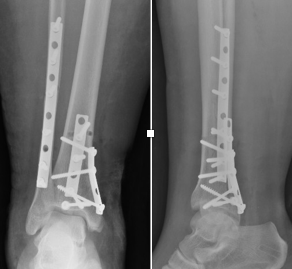

Artroplastia Total do Tornozelo

Cirurgia de substituição articular para tratamento da Osteoartrose do Tornozelo